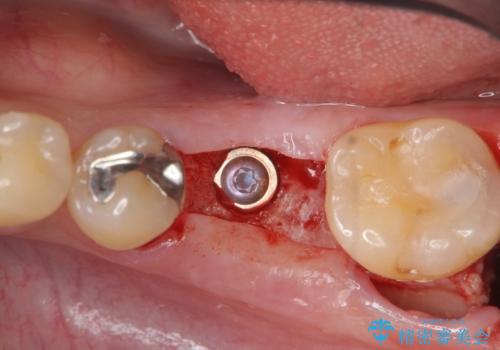

抜歯後、骨の再生を待ったことで、清掃性の高い位置に埋入を行い機能的・審美的なインプラント治療を行うことができました。